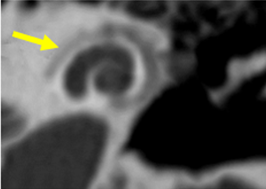

Figura 4. Vista de la ventana oval en un corte coronal del oído medio |

Figura 5. Ventana oval obliterativa de oído derecho en un corte coronal de oído medio |

El estado de la ventana redonda es importante, ya que su afectación se asocia a un mayor riesgo de hipoacusia neurosensorial posquirúrgica. La obliteración de la ventana redonda, aunque no se frecuente, puede diagnósticarse preoperatoramiente y podría contraindicar el tratamiento quirúrgico (Fig.6).

![]() |

|

Figura 6. Oídos derechos con obliteración de ventana redonda (flecha amarilla) |

Tamaño del nicho de la ventana oval: Valores de 1,4 mm se toma como límite inferior de la normalidad. Valores menores se asociaban con un riesgo mayor de tener dificultades técnicas durante la cirugía del estribo. Debe descartarse una otosclerosis obliterativa (Fig. 4-5). |

La evaluación mediante tomografía es fundamental para identificar los focos otoscleróticos, principalmente en la ventana oval a nivel de la fissula antefenestran, la cual es un surco que se localiza entre la ventana oval y el proceso cocleariforme. En la fase otospongiótica o activa de la otosclerosis, se pueden observar áreas hipodensas en el hueso, mientras que en la fase inactiva otosclerótica, se observara hueso compacto que puede afectar progresivamente la platina del estribo, provocando la fijación de este.

El grosor normal de la ventana oval se establece en 1.64 mm; valores superiores a 3 mm son considerados compatibles con otosclerosis. En un bajo porcentaje, alrededor del 10%, se presenta un subtipo retrofenestral, que afecta la cápsula ótica y puede resultar en desmineralización, lo que se clasifica como "otosclerosis muy avanzada", según lo definido por House y Sheehy.93 A continuación, se detallan las diferentes clasificaciones relacionadas con esta patología (Tabla 2 y 3).